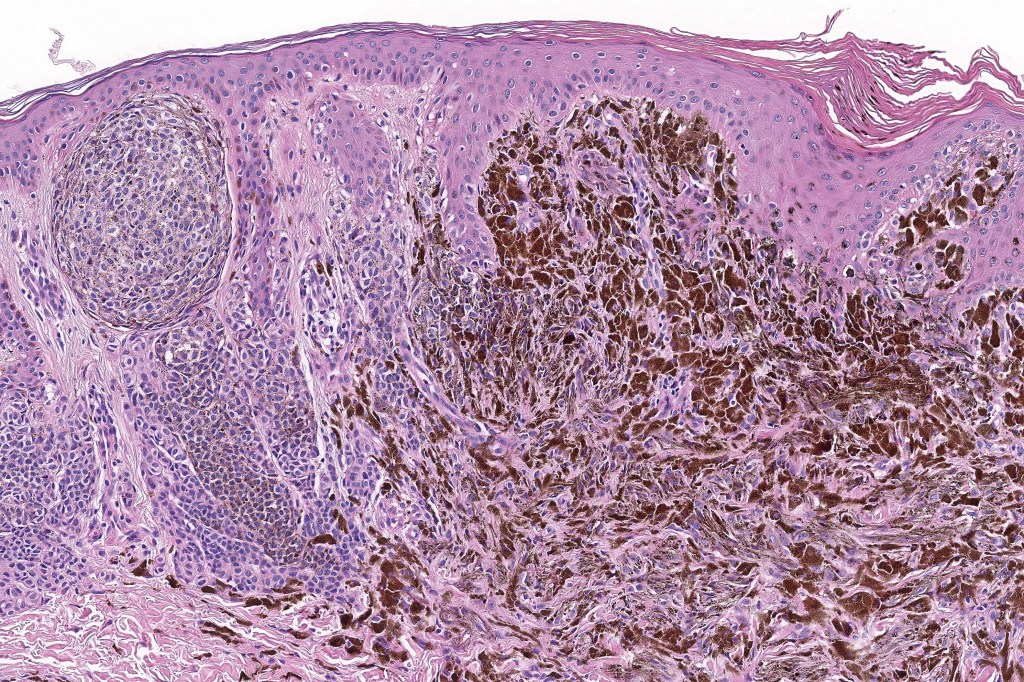

•Dermal of less often compound

•Wedge shape or less often plaque like silhouette

•Commonly associated with marked acanthosis/pseudoepitheliomatous hyperplasia although much less commonly, the epidermis is strteched over the lesion

•Composed of an admixture of large epithelioid melanocytes with vesicular nuclei containing a very prominent nucleolus (fried egg cells), spindle cells, dendritic cells & melanophages